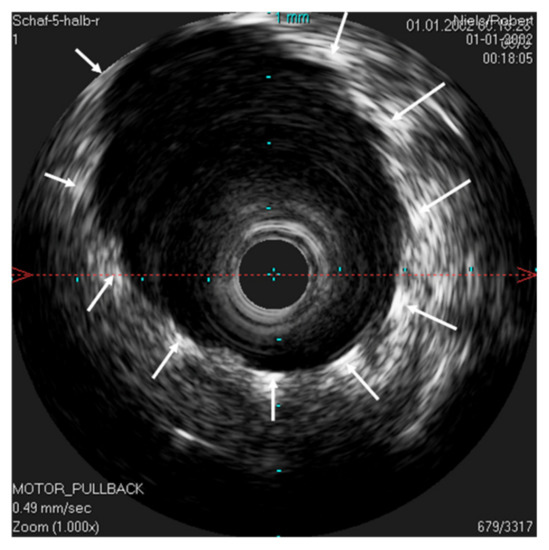

In order to possibly investigate the function of the ET, the lower jaw was moved manually during scans with a stationary IVUS catheter in the ET. An extension of the lumen and, thus, a size change of the lumen could be visualized (Figure 9) in the time-based longitudinal view. With the lower jaw closed, a lumen size of 3.21 mm2 was measured. The probe itself had a size of 1.33 mm2. With the mandible open, this lumen increased to 3.75 mm2. In the longitudinal view, this repetitive size change was clearly visible as waves.

Figure 9. Ultrasound image of the ET with a stationary IVUS probe. During the scan, the lower jaw was repeatedly moved manually, thus opening and closing the sheep’s mouth. Image (A) shows the ET over time. The lumen changes and movements of the surrounding structures can be seen as waves. Part (B) shows the cross-section of the tube with the mouth open, with an approximate tube lumen of 3.75 mm2, where the probe has an area of 1.33 mm2. Part (C) shows the same area with the jaws closed, where the tube lumen has decreased to 3.21 mm2.